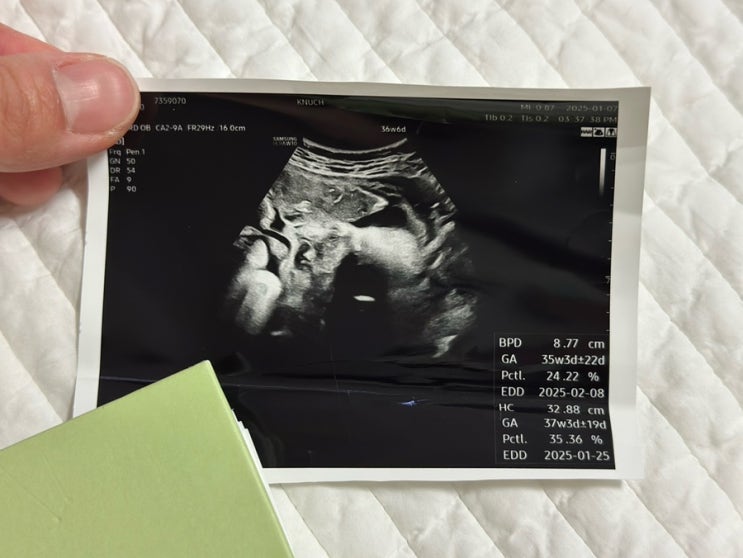

칠곡 경북대 병원 태아 심장 삼첨판 역류 심장 초음파 검사 후기

안녕하세요? @금미자 에요. 오늘은 칠곡 경북대 병원 신생아 심장 초음파 확인한 후기를 남겨볼까 합니다 :...

칠곡 경북대 병원 1박 2일 자연분만 후기

칠곡 경북대 병원에서 자연분만한 @금미자에요. 유도 분만 예정이었지만, 하루빨리 진통이 오는 바람에 자...

칠곡 경북대 병원 유도 분만 날짜 잡고 자연분만 한 썰. 둘째 출산 후기

임신 기록의 마지막! 둘째 지구별로 오다!!! 칠곡 경북대 병원 출산 후기를 남겨 볼까 해요. 저는 태아 심...